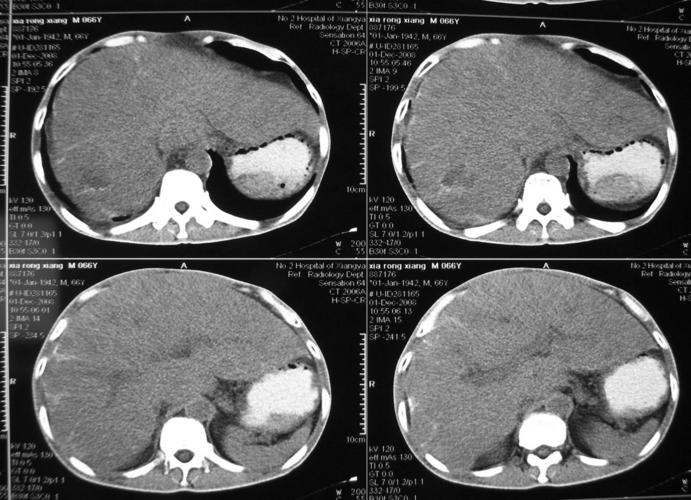

ct35592:男,66岁, 肝脏病变,请分析